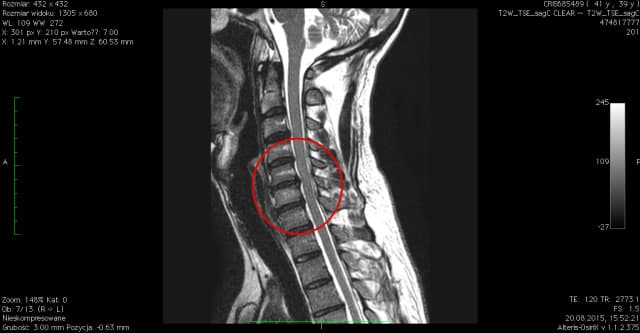

Przepuklina kręgosłupa szyjnego C6-C7: objawy i skuteczne leczenie

Poznaj objawy i skuteczne metody leczenia przepukliny kręgosłupa szyjnego C6-C7. Dowiedz się, jak rozpoznać dyskopatię szyjną i uniknąć powikłań. Sprawdzone informacje dla pacjentów.